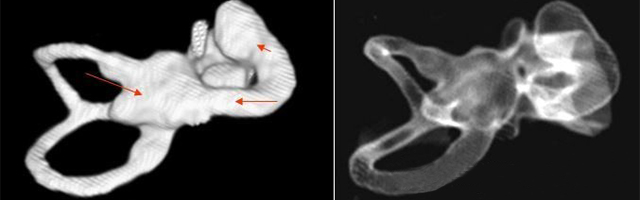

主要依靠顳骨高分辨CT和內耳MRI。

雙側內耳畸形:左側無內耳迷路及內耳道機構,為米歇爾畸形;右側空耳蝸及前庭擴大,為先天性耳蝸畸形